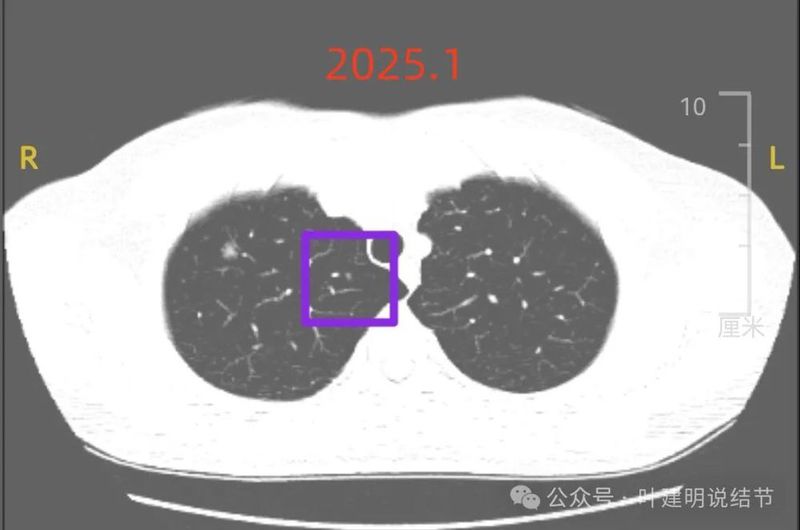

我们先来看2025年1月复查时说的右上1厘米病灶以及其他结节的情况:

病灶C:右上叶近纵隔侧距离肺门近点的位置另有实性小结节,密度高,膨胀感不明显,边界清,考虑良性可能性大些。

红色的是这次的,对比之前手术前的,这个病灶有明显增大进展,而且表面毛糙,内部密度欠均匀,如果从影像来看是要考虑微浸润性腺癌的。但奇怪的是,术前中叶的其他病灶也是像恶性的,磨玻璃密度,整体轮廓清楚,那还有空泡。病理怎么会是良性的呢?我觉得病理最好能会诊下。如果只看术前的,粉色的像原位癌,黄色的像不典型增生,绿色的密度过高像良性,紫色的微浸润性腺癌可能性大,要么慢性炎倒也可能。可你说之前手术病理不是恶性,那现在右上的也就也可能不是恶性。由于影像像恶性,病理不是恶性,这影响到右上进展的这个现在的病灶的性质判断。我的想法是:1、原来的手术标本最好能病理会诊一下(因为从影像看就像恶性的,当然预后是一样的,即便恶性也是切了就是治愈);2、可以考虑4~6个月再随访对比,如果继续进展或者呈现更加典型的恶性特征,那还是得干预;3、还有一种可能是细支气管腺瘤。另外再回复:紫色这个几年来没有进展,不像恶性。旁边还有黑色这处,密度过高,边缘较光,考虑淋巴结可能。我觉得只局部切了红色的就可以。意见供参考!